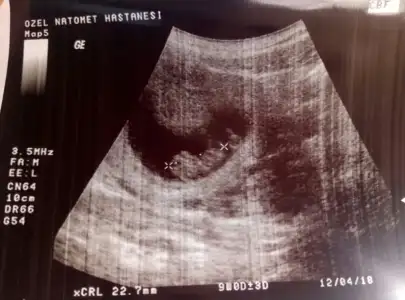

Kızlar merhaba buda benim fındığım 10 haftalık sizce ne tarafta benim kese biraz farklı sanki :KK37:o_O

Eklentiler

• IMG_7852.webp

IMG_7852.webp

8,2 KB · Görüntüleme: 153